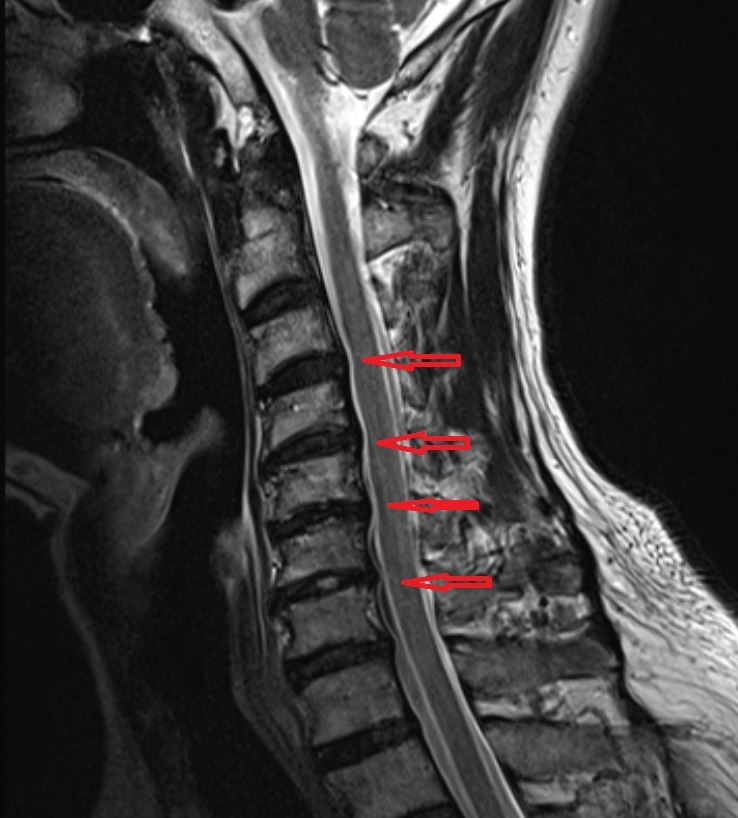

다음은 경추 디스크의 MRI 영상입니다. 돌출된 디스크가 신경을 눌러 증상을 유발하는 모습을 확인할 수 있습니다. 만성 경추 디스크의 경우 C6-7, C5-6 부위에서 신경근 압박이 가장 흔하게 나타납니다.

C6-7 신경이 압박되면 검지와 중지 방향으로 저린 느낌이 나타나기 쉽고,

C5-6 신경 압박 시에는 엄지손가락 방향으로 이상 감각이 나타나는 경우가 많습니다.

C7-T1 신경 압박 시에는 네 번째와 다섯 번째 손가락 방향으로 방사통이 나타날 수 있지만, 실제 임상에서는 이 부위 저림이 경추 디스크 외 다른 원인과 함께 나타나는 경우도 많습니다.